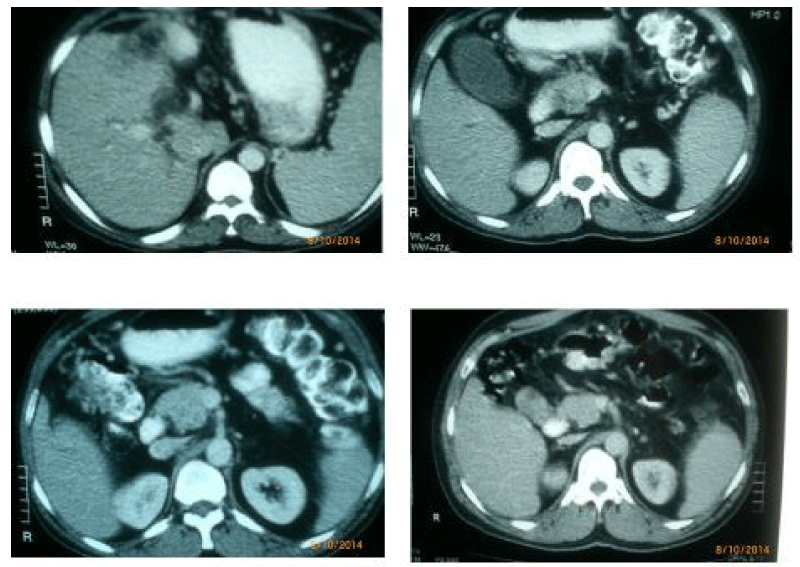

A 45 year old, diabetic male patient presented with upper abdominal pain, significant weight loss and obstructive jaundice of 2 months duration. He also had fever with chills of 25 days duration. There was no history of pulmonary or lymph nodal tuberculosis in the past. Liver function test was found to be altered and in favor of obstructive jaundice. CECT abdomen revealed a irregular hypodense mass in the pancreatic head with infiltration of the uncinate process and was abutting superior mesenteric vein (Figure 1). The Common Bile Duct (CBD) was found to be grossly dilated and Pancreatic Duct (PD) marginally. Upper GI Endoscopy showed no ampullary lesion or narrowing of the 2nd part of the duodenum. CA 19-9 was 36.5 U/ ml. Chest x-ray was normal. He underwent laparotomy where in a mass lesion was found in the head and uncinate process of the pancreas, with infiltration of the Superior Mesenteric Vein (SMV). There was hepatomegaly with dilated peri-gastric collaterals. Incision biopsy was taken from the uncinate process. Roux-en-Y choledocho-jejunostomy was done to relieve jaundice. Histopathology revealed numerous caseating epithelioid granulomas amongst pancreatic acini suggestive of pancreatic tuberculosis. No acid fast bacilli were seen. The tissue was not subjected to culture, but tissue polymerase chain reaction assay was positive for mycobacterial DNA. Postoperatively patient recovered uneventfully and was administered anti-tuberculous therapy for 9 months, which consisted of pyrazinamide, ethambutol, rifampicin, isoniazide for two months followed by isoniazide + rifampicin for rest of the period. Serum bilirubin reduced to 11.7 mg% from 3.77 mg% in 3 weeks. At one year post- surgery, the patient was asymptomatic and had improved his weight. CT scan repeated at one year also showed complete resolution of the head mass. At 3 years follow-up he was well and asymptomatic (Figure 2).

Figure 1: Contrast enhanced abdominal CT scan showing mass in the head of the pancreas with its close relationship to superior mesenteric vein. Also seen is the distended gall bladder.